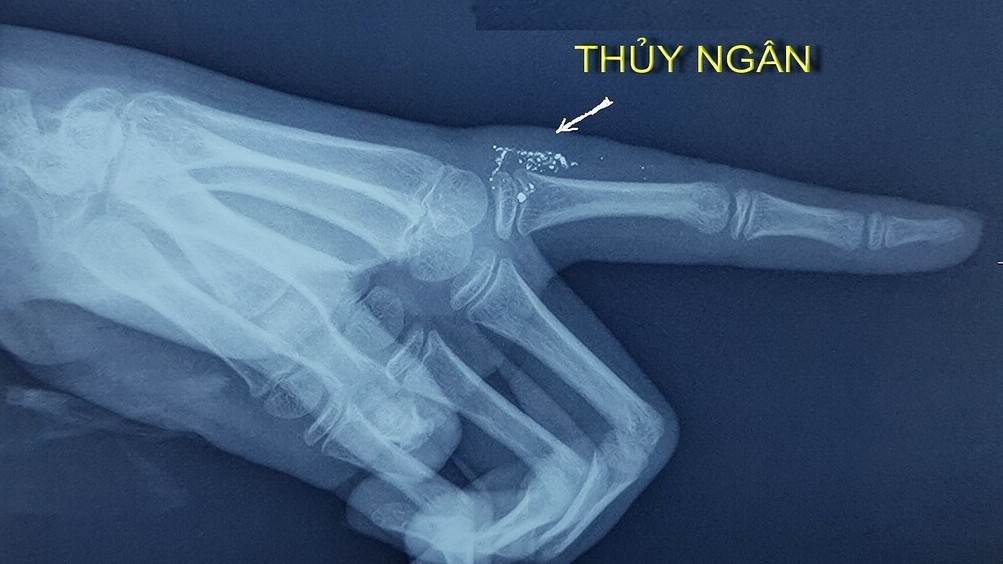

Khi được đưa tới Bệnh viện Bạch Mai, vết thương của bé đã bị nhiễm trùng và áp xe. Hình ảnh chụp X-quang cho thấy ngón tay của bé có nhiều hạt thủy ngân ở bên trong phần mềm sát khớp bàn ngón trỏ tay...